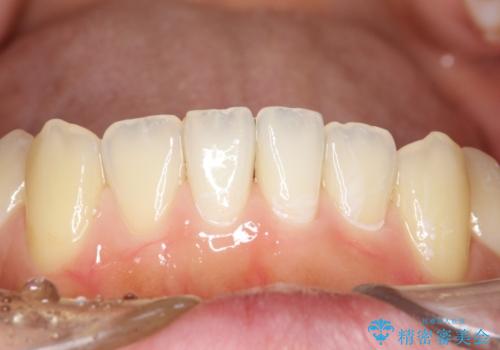

茶渋による汚れをクリーニングできれいに

PMTCというクリーニングを行うことでステインは除去できるので、今回はPMTC(エアフロー)の60分コースにて全体のクリーニングを行いました。

エアフローは歯と歯の間や、詰め物との境目などブラシやチップが届かないところまで細かくお掃除が可能になります。

隅々までお掃除することで虫歯や歯周病のリスクを下げる効果があります。